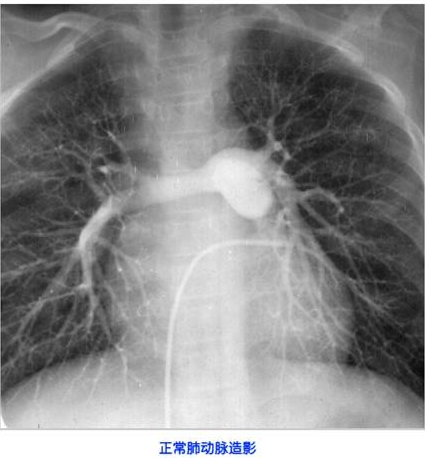

照片名称:正常肺动脉造影